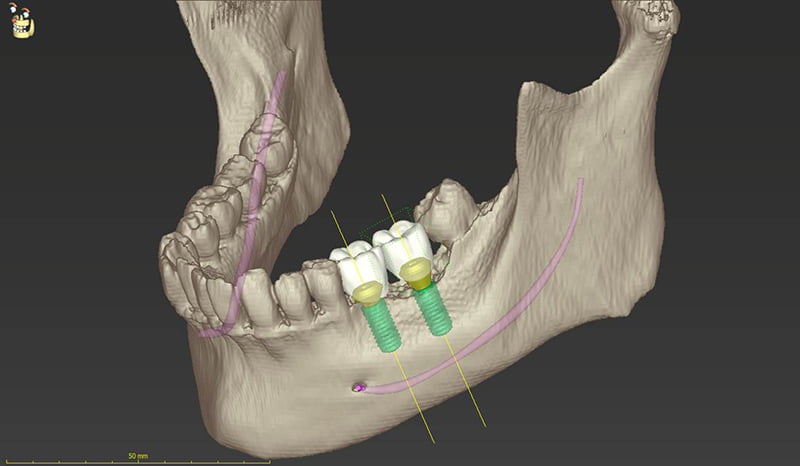

インプラント治療を行う上で最も大切なこと、それは「診断」です。CTやシュミレーションソフトを用いて事前に「骨の形態」「血管の位置」などを正確に把握し、適切な診査・診断を行うことで、安心安全なインプラント埋入位置を正確に決定することが出来ます。このようにインプラントによって出来上がる歯の位置を中心に治療計画を立てて治療を進めることを "トップダウントリートメント" といいます。

長期的予後の良いインプラント治療を行うためには、トップダウントリートメントによりその部位に正確にインプラントを入れる必要があります。